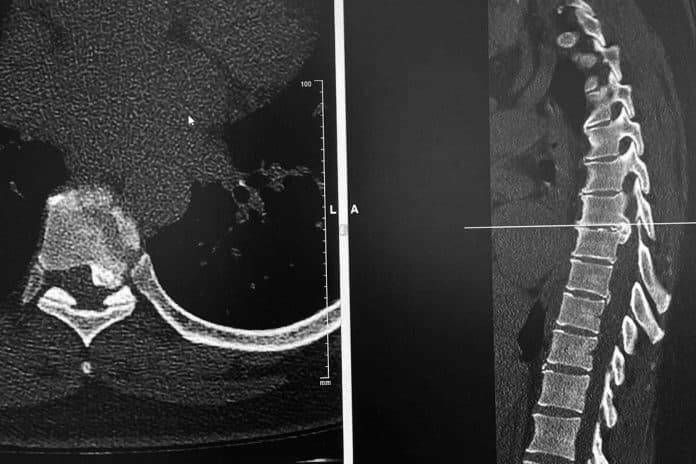

Los discos dorsales son tejidos semejantes a un cojín esponjoso que se encuentran entre las vértebras de la columna. Las hernias aparecen cuando uno de los discos sobresale de entre las vértebras, presionando los nervios y la médula, lo que produce dolor y otros síntomas como la sensación de hormigueo, dependiendo del lugar en el que se originen.

Es común que con la edad, el material gelatinoso que amortigua los discos se debilite y desaparezca, posibilitando movimientos que los desvíe de su posición original, produciendo de esta manera una hernia. Cuando el disco llega a presionar la médula o algún otro nervio importante, es posible que el paciente presente sensación de adormecimiento en las extremidades y, en casos más graves, debilidad en las extremidades o dificultad para el movimiento.